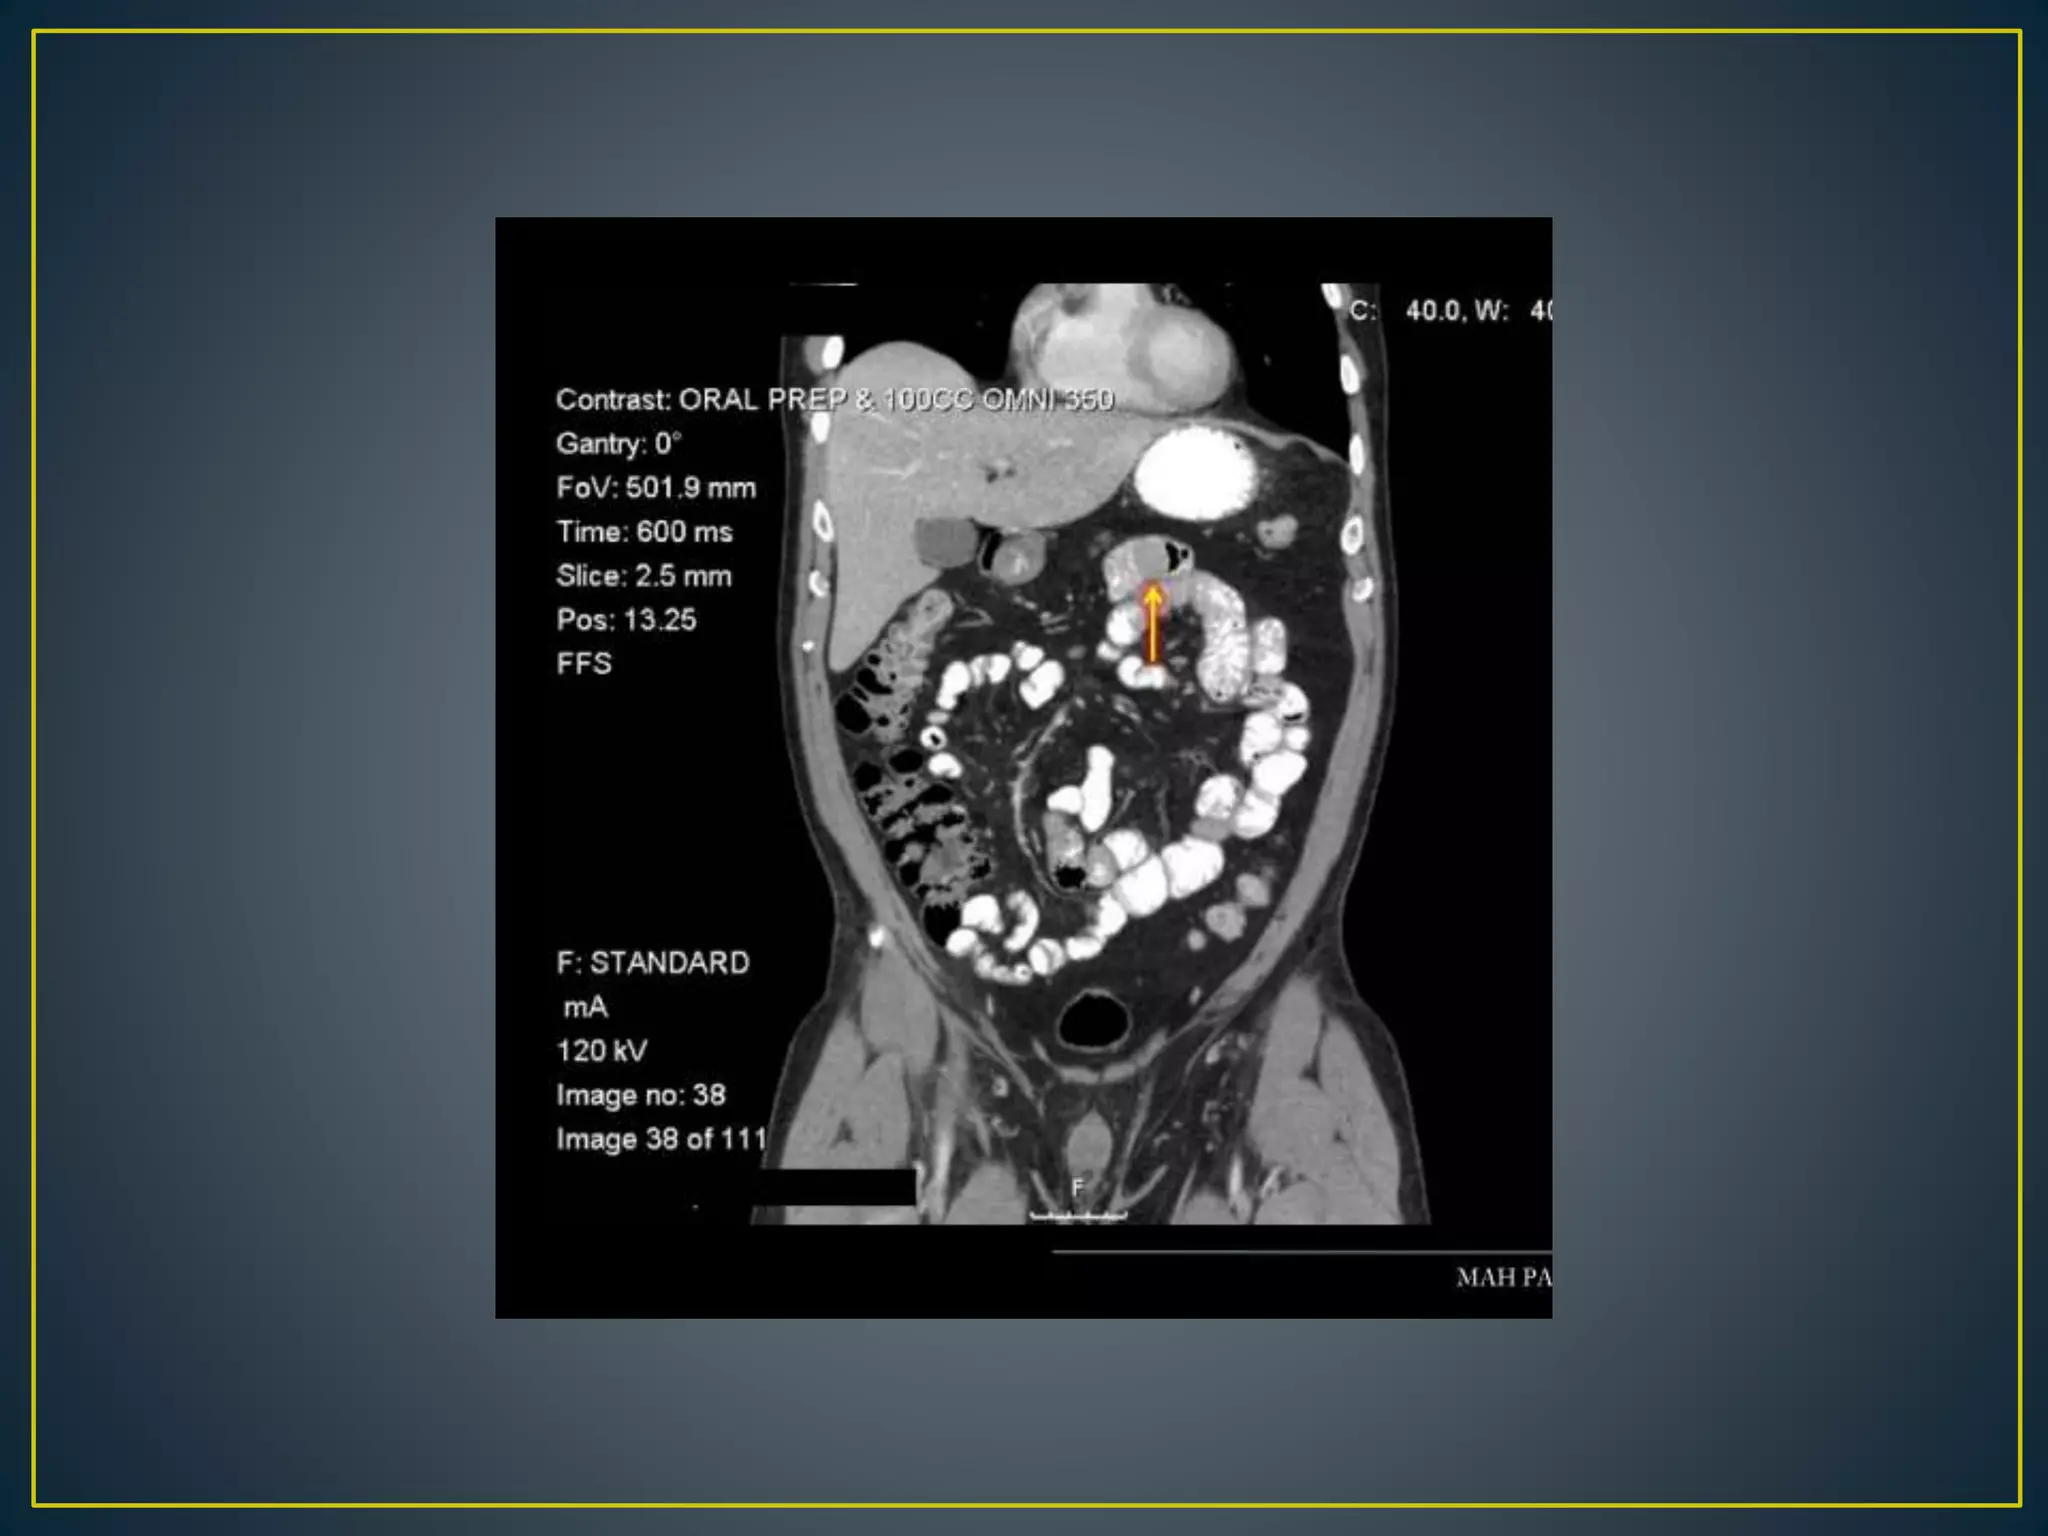

• Recent advances in CT technology allowing thinner

collimation, faster scanning times, greater anatomic

coverage, and better multi-planar reformatted (MPR)

images have greatly expanded the diagnostic role of CT

angiography for GI BLEEDING

• The CT angiographic diagnosis of active gastrointestinal

bleeding is made when hyper attenuating extravasated

contrast material is seen within the bowel lumen . The

extravasated contrast material may demonstrate linear,

jet like, swirled, ellipsoid, or pooled configurations or may

fill the entire bowel lumen, resulting in a hyper-

attenuating loop